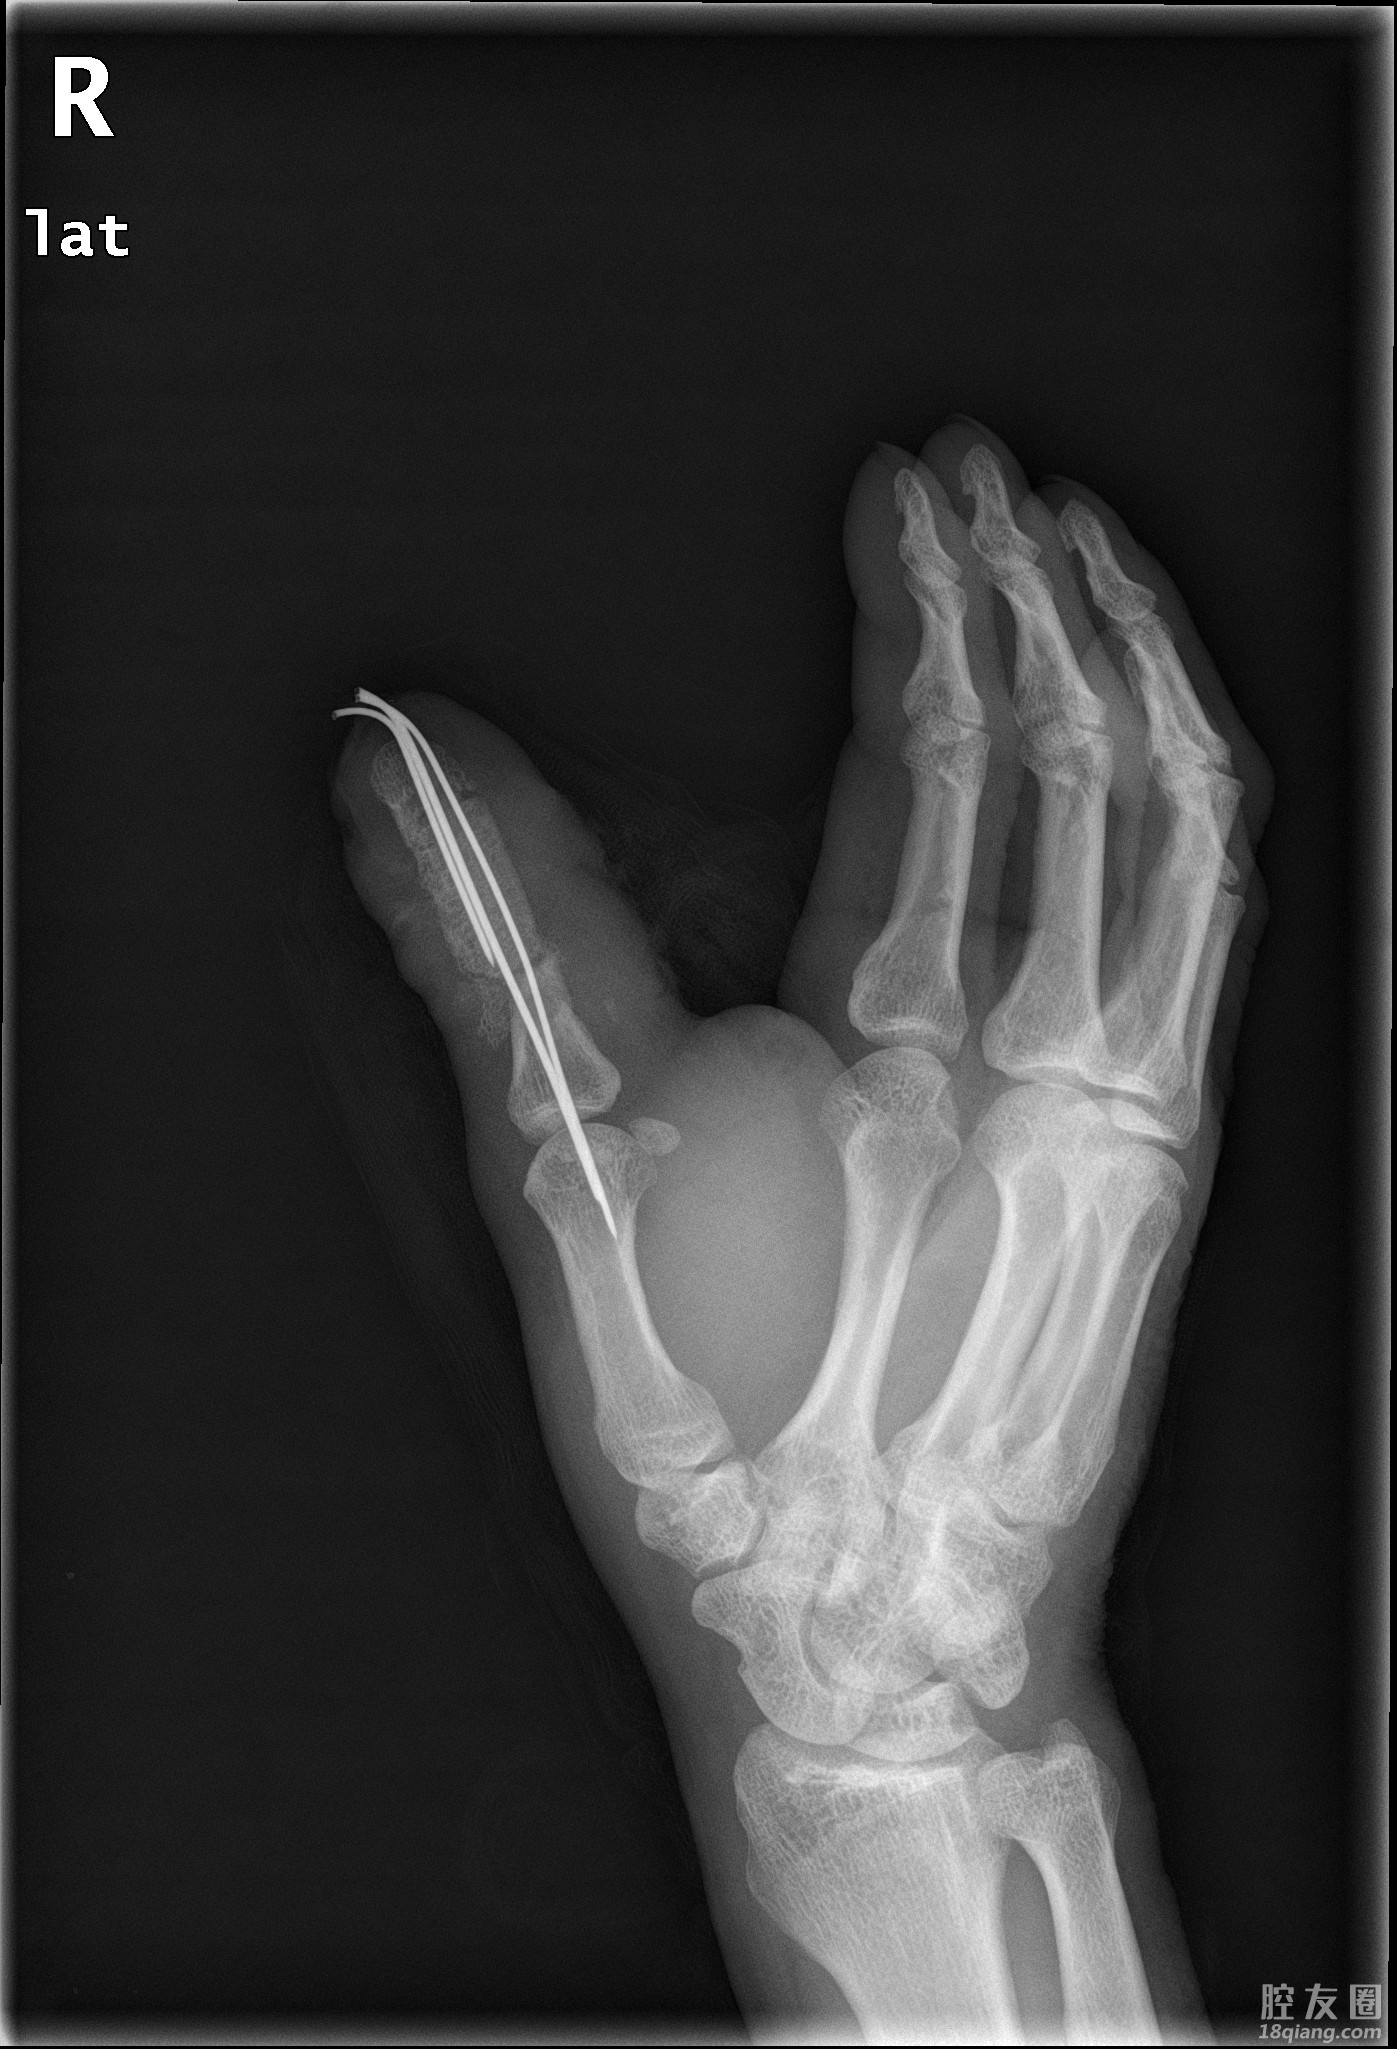

手术中,杨锦主任医师团队小心游离解剖右踇趾血管神经,游离髂骨组合移植,以最大限度保证再造大拇指的长度和功能,又能大大降低对右足踇趾供区的破坏。

手术的关键是显微镜下的精细操作,需要用相当于头发丝三分之一粗细的缝合线进行神经、血管的吻合,每一步都需要精细再精细、严谨再严谨。经过手足外科团队的艰苦奋战,再造的手指外观接近正常手指,血管吻合一次通血成功,血运良好,指体红润、饱满,团队成功完成拇指全形再造手术。